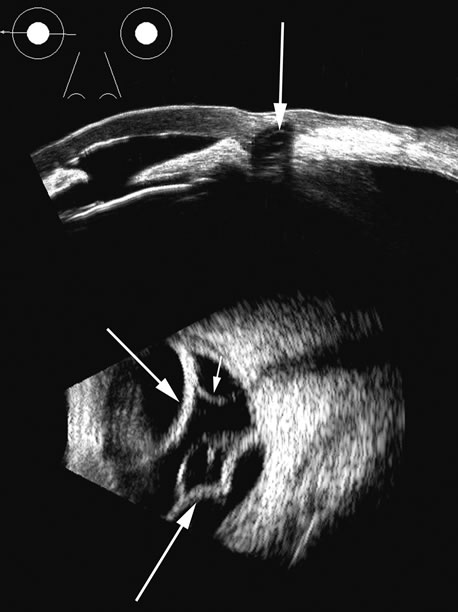

Hypotony is easily diagnosed by direct measurement of intraocular pressure, but the underlying cause is difficult to evaluate.11 High-frequency ultrasound scans can easily reveal separation of the ciliary body and the sclera. This allows different forms of hypotony to be determined—for example: tractional with membrane attached; primary as idiopathic, often inflammatory or hemorrhagic; and dehiscence secondary to iridodialysis or scleral perforation (Fig. 6).

Fig. 6. Hypotony of the eye generally is easily diagnosed by a separation of the ciliary body from the sclera. We have noted several types of such separation, such as tractional, primary (idiopathic), and dehiscence secondary to iridodialysis or scleral perforation, as in filtration procedures. In our series, greater than two clock hours of separation is typical of hypotony. The lower figure shows a concomitant thickening of the retina-choroid complex, also seen in hypotony (arrows). Long-standing hypotony typically has a shortened globe and possible retinal or choroidal separation.